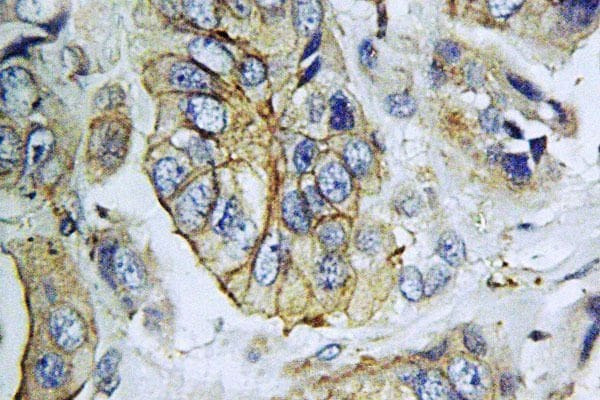

- Immunohistochemistry analysis of NPY5R in paraffin-embedded human breast carcinoma tissue. Samples were incubated with NPY5R polyclonal antibody (Product # PA5-75355).